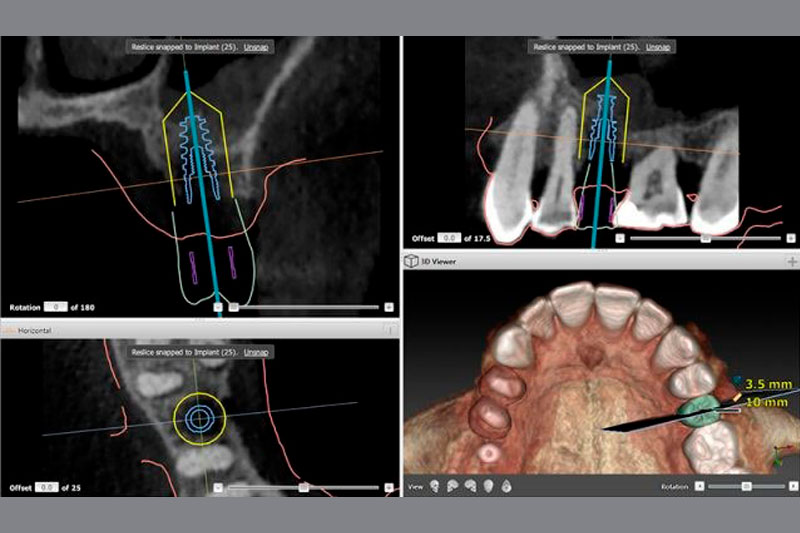

En Clínica Dental Oliver Coll utilizamos la cirugía guiada por ordenador 3D, la técnica más avanzada en implantología que nos permite:

PLANIFICACIÓN VIRTUAL PREVIA

Mediante un escáner intraoral 3D y un TAC dental, estudiamos tu caso con absoluta precisión antes de realizar cualquier intervención. Planificamos virtualmente la posición exacta de cada implante.PRECISIÓN MILIMÉTRICA

Colocamos los implantes exactamente donde deben estar, con una precisión de hasta 0.1 mm, evitando nervios, senos maxilares y garantizando el mejor resultado estético.- CIRUGÍA MÍNIMAMENTE INVASIVA